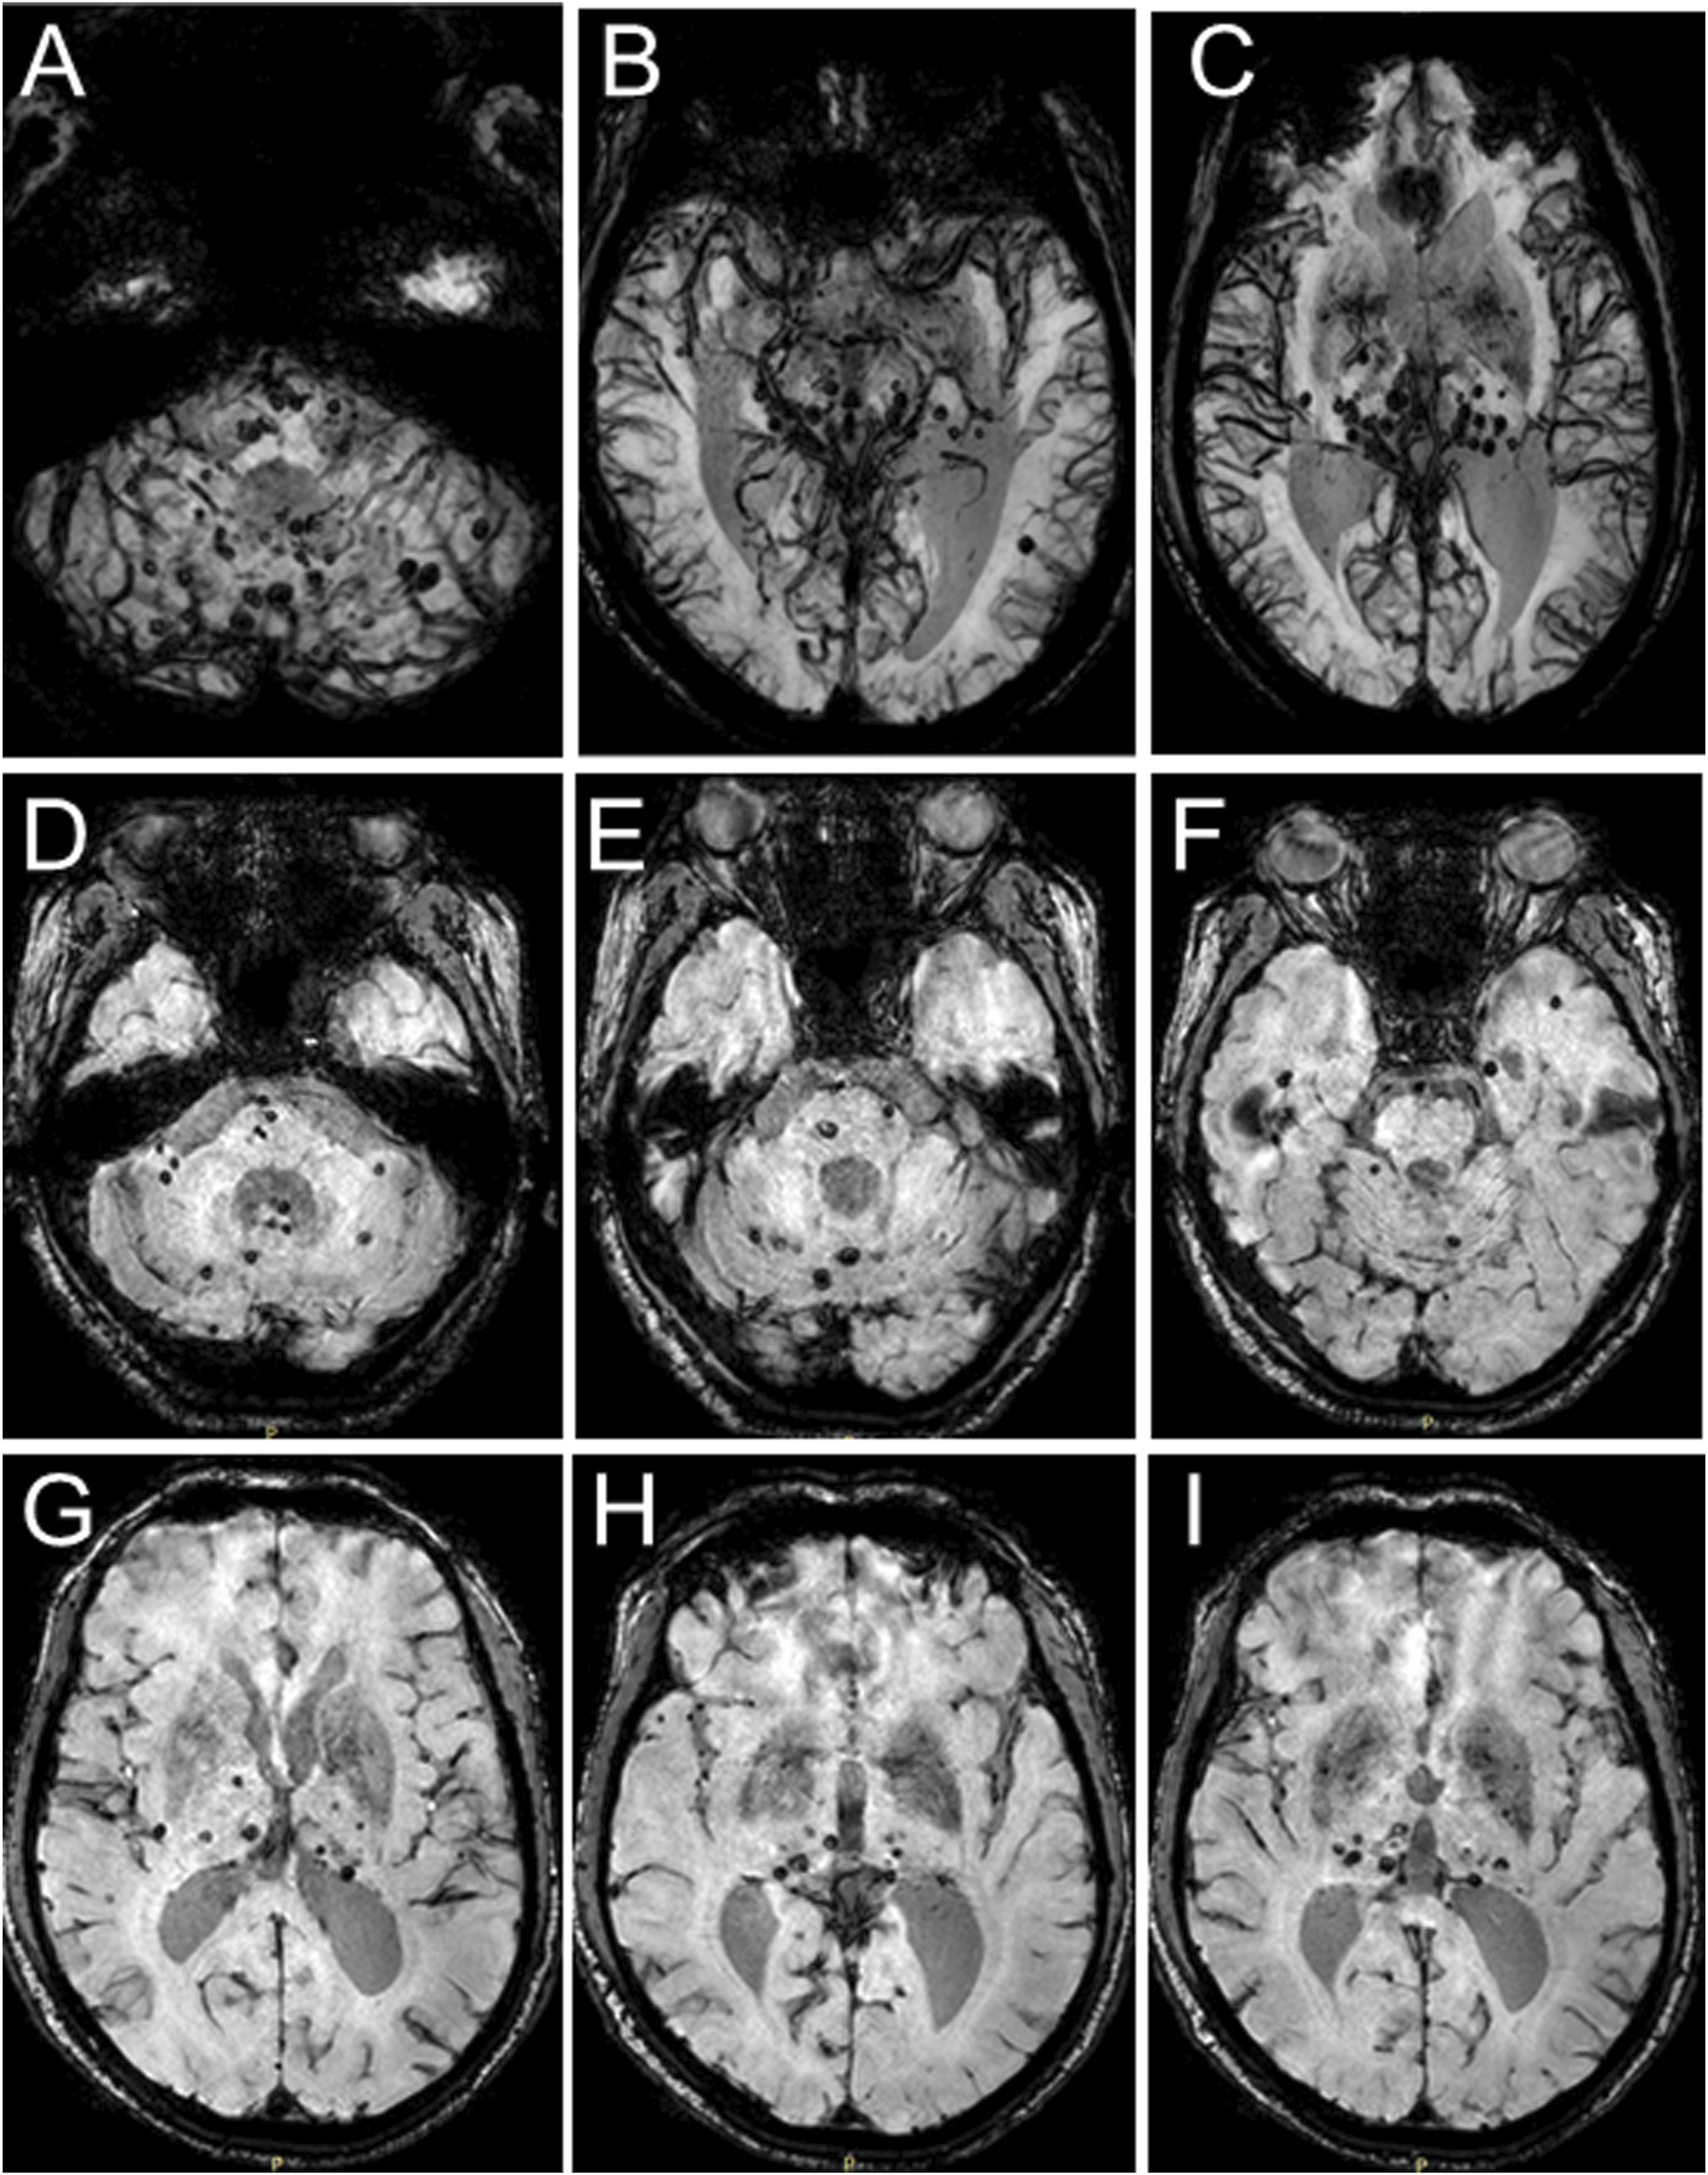

In 2018, the proband (67 years of age) suffered his first acute ischemic attack, an acute cerebral infarction at the left edge of the brainstem. Then, 10 months later (May 2019), he developed multiple small intracranial hemorrhages. Subsequently, in September 2019 (the 11th hospitalization), he experienced an acute ischemic attack again, an acute lacunar infarction in the right basal ganglia and radio-corona. The main symptom was weakness in both legs, accompanied by transient reaction dullness, difficulty in speech expression, speech disorder, and partial impairment of understanding. Results from a brain CT scan suggested multiple lacunar cerebral infarctions, white matter degeneration, and brain atrophy (Figures 1A–D). Significant high-density signals were observed in the brain DWI (diffusion weighted imaging), suggesting acute ischemic lesions in the right basal ganglia region and radio-corona region (Figures 1E, F). The brain stem, basal ganglia, and multiple luminal infarcts in the thalamus could be readily observed on the T1-weighted imaging with decreased signal intensity (Figures 1G–I). T2-weighted and FLAIR (fluid-attenuating inversion recovery) brain MRI revealed symmetrical white-matter lesions in the temporal pole, outer capsule, lateral ventricle, and deep brain (Figures 1J–L). Additionally, the SWI (susceptibility weighted imaging) revealed multiple low signals, which were thought to be micro-bleeding (Figures 2A–I). His craniocerebral DSA (digital subtraction angiography) examination revealed multiple things. First, a slight stenosis of the left internal carotid artery in the siphon segment was found, as well as multiple moderate-to-severe stenosis of the right anterior-cerebral artery and multiple mild-to-moderate stenosis of the left-middle cerebral artery. Second, multiple mild-to-moderate bilateral-posterior cerebral artery stenoses were identified, as well as a bilateral-superior cerebellar artery with multiple moderate stenosis (Figures 3A–C).

FIGURE 2

Brain MRI-SWI images of the proband. SWI images present with multiple hypointense signal intensities at several brain levels and demonstrate multiple foci of hemorrhage in the proband’s brain.